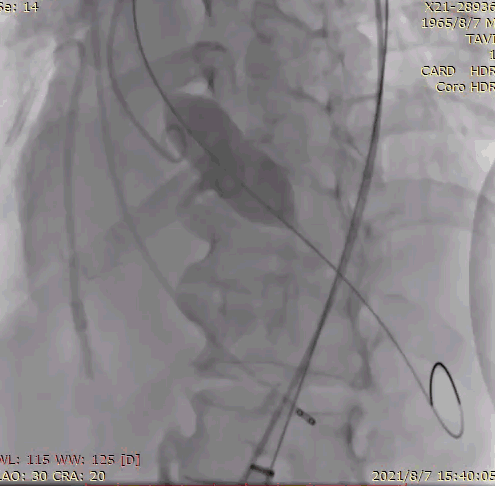

7.根据术前评估及球囊预扩情况,选择 26mm 沛嘉 TaurusElite 瓣膜进行植入,第一次展开瓣膜位置偏下,全回收一次再次展开瓣膜,在 130 次/分快速起搏下释放瓣膜,同时将冠脉支架拉至左冠开口外约 9mm 处释放;

因此,在手术策略的制定上,我团队根据患者瓣环平均径及周长数据(24.0mm/79.1mm),基于高钙化患者 down size 方案及降低冠脉封堵风险考虑,选择了 26mm TaurusElite 瓣膜进行植入。术中采用 22mm TaurusAtlas 球囊预扩后,显示轻微腰征,造影无渗漏,左冠开口显影不明显,验证了术前判断。遂预埋冠脉支架,行烟囱支架置入术。

瓣膜过弓、释放过程相当顺利,大手柄具有的良好操作性,帮助术者进行了精确的释放定位。

在释放末段,通过牵拉冠脉支架完成 TAVR-烟囱支架置入术。术后即时造影示少量瓣周漏,测量跨瓣压差示平均压差 12mmHg。经讨论,考虑到冠脉支架与瓣膜自膨胀支架可能存在接触间隙,遂行球囊后扩。后扩后跨瓣压差进一步降低,得到理想的手术效果。